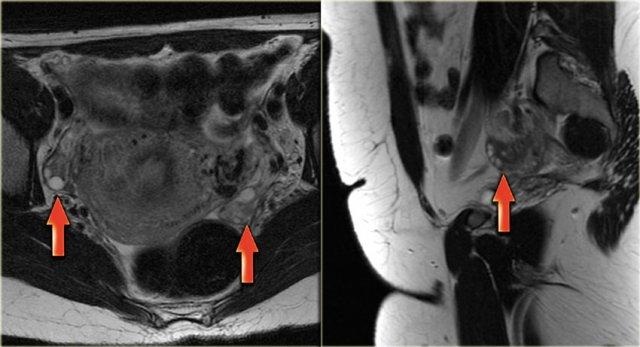

TRÁI: Phụ nữ sau mãn kinh. Buồng trứng là một cụm mô giảm tín hiệu T2W nằm gần đầu gần của dây chằng tròn. PHẢI: Buồng trứng trái giảm tín hiệu T2W, không có nang noãn. Buồng trứng hơi nổi bật nhưng vẫn có khả năng là bình thường

Sau mãn kinh

Mãn kinh được định nghĩa là vô kinh kéo dài 1 năm hoặc hơn. Ở các nước phương Tây, độ tuổi mãn kinh trung bình là 51-53 tuổi.

Ở phụ nữ sau mãn kinh, buồng trứng thường nhỏ hơn và dần dần ngừng hình thành các nang Graaf.

Tuy nhiên, cần lưu ý rằng các nang noãn có thể tồn tại trong vài năm sau mãn kinh.

Trên ảnh MRI chuỗi xung T2W mặt phẳng coronal của một phụ nữ sau mãn kinh, buồng trứng chỉ là một cụm mô giảm tín hiệu nằm gần đầu gần của dây chằng tròn.

Ảnh MRI chuỗi xung T2W mặt phẳng axial cũng cho thấy buồng trứng trái giảm tín hiệu, không có nang noãn.

Mặc dù hơi nổi bật, đây có khả năng là hoàn toàn bình thường.

Chỉ khi tình cờ có hình ảnh trước đó cho thấy tổn thương đang phát triển, chẩn đoán phân biệt mới bắt đầu với các tổn thương đặc lành tính như u xơ buồng trứng hoặc u xơ-vỏ buồng trứng.